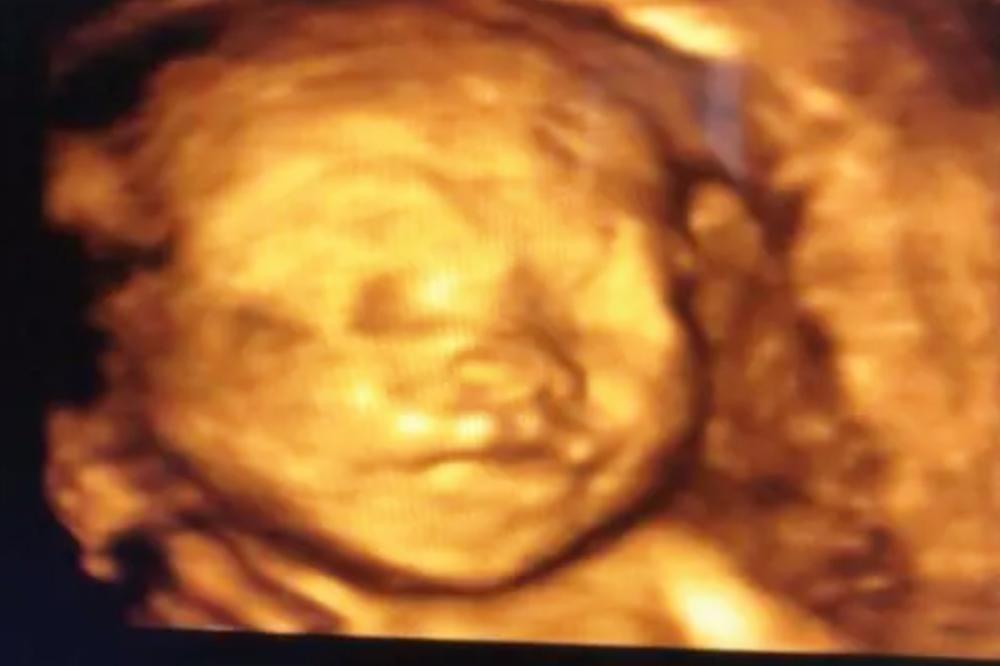

怀孕期间会有几次B超的检查,只有在四维检查的时候是可以看到孩子的样貌的 。很多人第一次看到四维照片时候,都会惊呼孩子太丑了。等到孩子出生后,再回头看看四维照片更是惊呆。

不仅大家好奇,小雪自己也是充满了期待。终于等到了24周做大排畸,可以有机会看到孩子的样貌了。满怀期待地做完了检查,看到四维单子上的图片的时候,小雪差点没哭了。

因为孩子的样貌实在是太“丑”了, 鼻子塌塌的一点没有遗传老公高高的鼻梁,眼睛也紧紧地闭着看不出来大眼睛的样子,而且整张脸都是皱巴巴的。

四维检查是通过声波的反馈给出的图形显示,并不是真的透过妈妈的肚子看到了孩子的样貌。 四维的检查是需要不断移动仪器来判断的,这个过程不排除羊水、脐带等会对反馈的图片造成干扰,导致孩子的样貌形成有偏差。

虽然很多人看到出生的孩子和四维很像,但仔细分辨看还是有很大差别的。 即便是成人通过四维扫描拍出来的照片也不会太好看,何况是小婴儿。